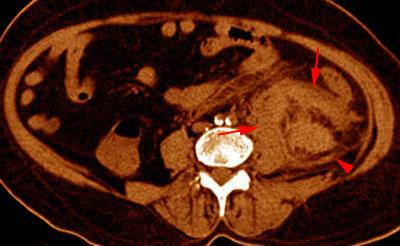

Hematoma subcapsular